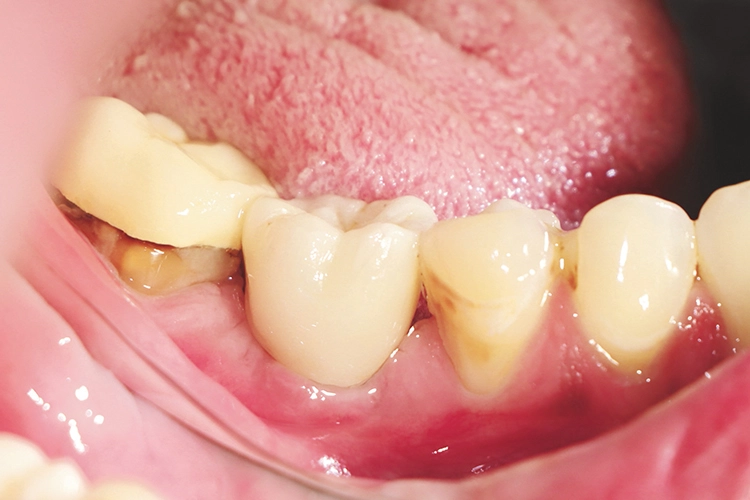

Eine Patientin (33 Jahre), Gelegenheitsraucherin (3 bis 7 Zigaretten/day) und Z.n. Thrombose im Jahr 2009, mit insgesamt unauffälliger Allgemeinanamnese kam im Juni 2020 als Schmerzpatientin in unsere Praxis. Ausgehend von Zahn 46 litt sie an einem PA-Abszess (Abb. 1).